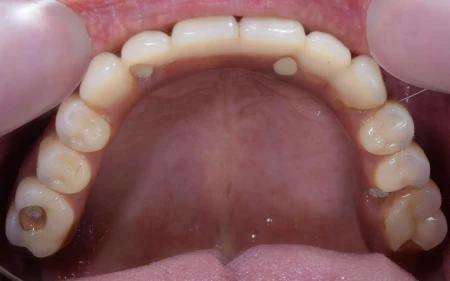

上のAll-on-4の写真です。 厚みはほとんどなく、入れ歯のような分厚さもありません。 固定式ですので、硬い物でも何でも食べられるようになりました。 使用感にとてもご満足いただいています。

入れ歯と違って厚みも非常に薄いのが特徴です。 天然歯と遜色なくお使いいただけます。